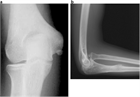

1. 投球動作などに起因する慢性靭帯損傷では、まず、理学療法などを中心にした保存的治療を行うことが推奨される。

1. 肘関節不安定性が持続する慢性靭帯損傷では、靭帯再建術を行うことが推奨される。